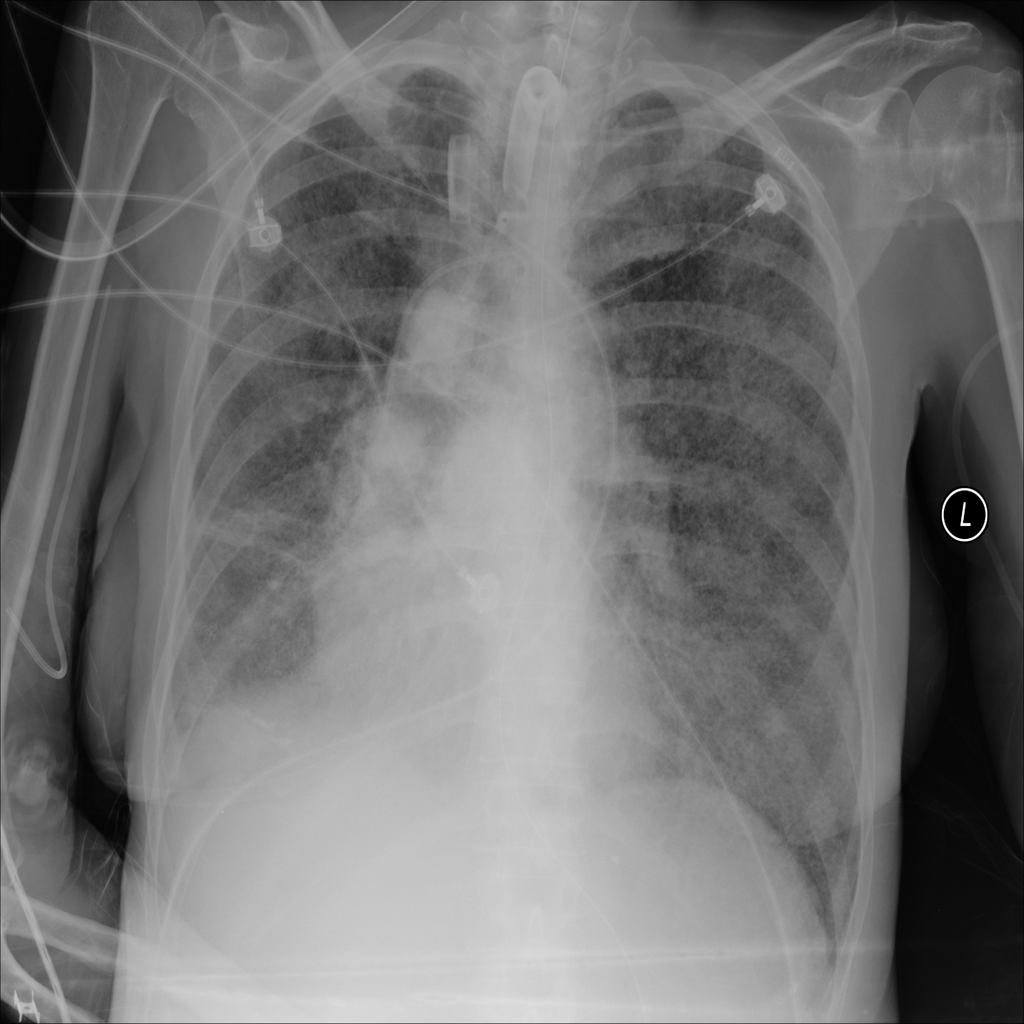

PAT-E960 · IMG-002Fibrosis

PAT-E960 · IMG-002

PA